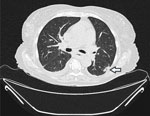

Patient 2 was an 82-year-old woman who was referred to the University Hospital Cologne with a diagnosis of acute myeloid leukemia 5 months before admission (Table). She had been treated with azacitidine monotherapy, but after allergic transfusion reaction to platelets, her cancer treatment was discontinued. At admission, the patient was experiencing hyperleukocytosis and neutropenia. We initiated cytoreductive treatment with hydroxyurea. A baseline chest CT scan revealed nodular infiltrates and a subpleural cavitary lesion, suggestive of fungal pneumonia (Figure 1). Of note, the patient had not received any antifungal prophylaxis other than trimethoprim/sulfamethoxazole. Bronchoscopy demonstrated purulent secretions. Results of galactomannan testing of BAL fluid were positive; culture yielded a preliminary phenotypic identification of Geotrichum spp. All other diagnostic work-up results were unremarkable (Table). Given the clinical significance of the mold identification, we pursued further species-level analysis. ITS sequencing identified the organism as either B. adusta or B. fumosa (10). Aspergillus PCR was negative. We could not perform antifungal susceptibility testing because of insufficient fungal growth. We initiated voriconazole therapy but switched to isavuconazole because the patient experienced visual disturbances. Follow-up chest CT scans at 2 and 5 weeks showed stable disease. After 5 weeks of antifungal therapy, we discontinued treatment and initiated posaconazole as secondary prophylaxis. No additional follow-up visits occurred.